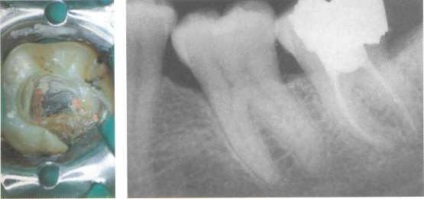

Ábra. 45. Gyökértömés.

Ha nincs csatorna lehet lezárt panaszok gutta-Perch és a dugónak a latte-ponti kondenzáció. Coron-kovuyu üreg kitöltése állandó helyreállítása.

Bal: A guttapercha levágjuk a szájukat a csatornák, az üreg tisztán.

Ábra. 46. Két évvel később. Ezen a fogat röntgenfelvétel 2 év után endodontális kezelést határozzuk normál periodontális rés a csúcsa nélkül a gyulladás jeleit. Azonban van egy kis lokálisan-ver vákuum közötti a mag-Nyami.